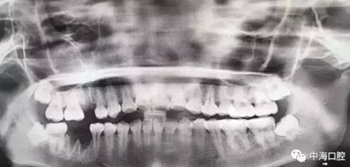

由于智齒的生長位置特殊,導(dǎo)致了拔除難易不同,如智齒出現(xiàn)橫著長或者靠近牙神經(jīng)的話,則難度會較高,一般人只需拍個口腔全景片,但相對于智齒靠近神經(jīng)管的情況,還可能需要拍CT,這都很考驗牙醫(yī)的技術(shù)。

下面這兩張圖,據(jù)說拔牙費時1.5小時,收費14000元。